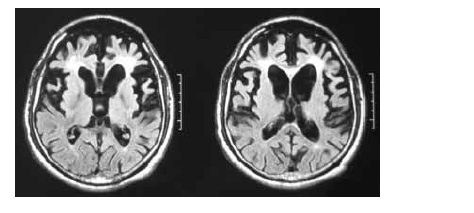

Uma mulher de 55 anos de idade, sem comorbidades, há três anos começou a apresentar distúrbio do comportamento, comprometimento do senso moral, da autocrítica, do poder de abstração e da memória. No exame, ela pouco colaborava com o examinador, possuía uma rigidez axial e apendicular, além de sutil tremor em repouso. O exame de imagem (RNM) a seguir foi realizado para auxiliar o diagnóstico.

Com base nesse quadro clínico, julgue os itens subsequentes.